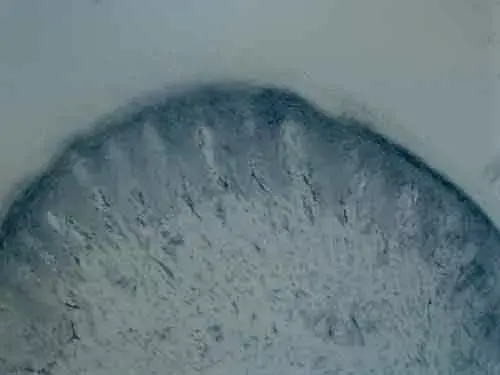

Rabbit Polyclonal Tyrosine Hydroxylase antibody. Suitable for WB, IHC-FoFr, ICC/IF, IHC-P and reacts with Mouse, Rat, Human samples. Cited in 5 publications. Immunogen corresponding to Recombinant Fragment Protein within Human TH aa 150-500.

Applications ICC/IF, IHC-FoFr, IHC-P, WB

Species Reactivity Human, Mouse, Rat